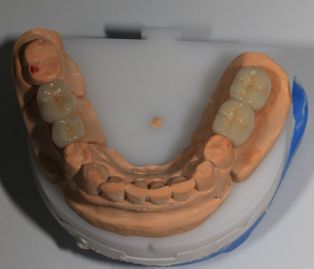

Во время операции вам устанавливают в челюсть 4,6 либо 8 имплантатов. Если на момент операции в челюсти находятся зубы, подлежащие удалению, то их (непосредственно перед имплантацией) удалят. Далее вы отдыхаете после операции в индивидуальной палате под наблюдением медицинской сестры и врача-анестезиолога, а в это время зубной техник в зуботехнической лаборатории изготавливает вам временный несъемный протез (состоящий из 10-14 искусственных зубов).

Этап 4. Постоянное протезирование

Замена временного протеза на постоянный производится через 3-6 месяцев с момента операции и зависит от скорости приживления имплантатов. Несмотря на то, что временный протез может служить Вам до 3х лет, если вдруг по финансовым причинам вы не сможете в такой срок позволить себе изготовление постоянного несъемного протеза, мы рекомендуем установку постоянного протеза ввиду его гораздо более качественного исполнения, лучшего внешнего вида и функциональности.

Изготовление временных и постоянных протезов для большинства концепций производится прямо в зубо-технической лаборатории MEDALL, однако для протокола Allon4 постоянный протез выполняется на оригинальной балке Procera, обеспечивающей существенно большую надежность конструкции  и будет состоять уже не из 10, а из 12-14 искусственных зубов, и сделан не из акриловой пластмассы, а из металлопластмассы, металлокерамики, либо диоксида циркония (безметалловой керамики). Последний вариант стоит весьма дорого, но обладает потрясающей эстетикой и практически не отличим от настоящих зубов.